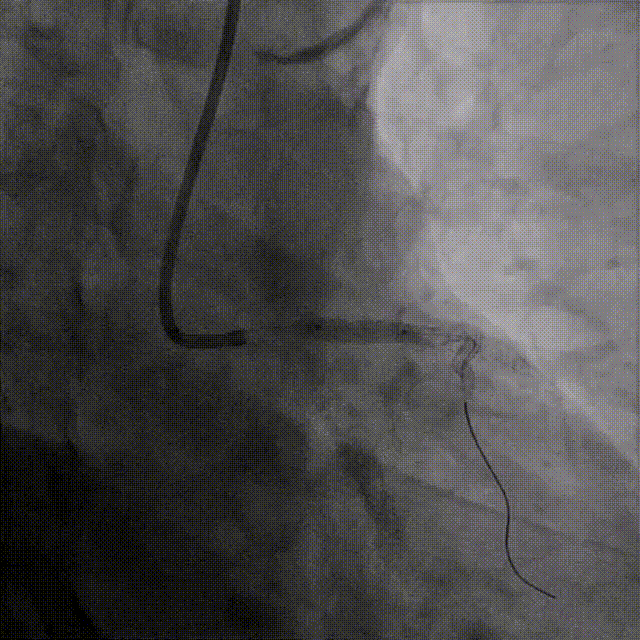

LAD植入支架

LAD由远及近植入2.75*33mm、3.5*23mm、3.5*18mm支架

球囊后扩张

LAD分别送入3.0*15mm、4.0*15mm、4.5*15mmNC球囊扩张病变处

经后扩复查IVUS

-

LAD中远段支架贴壁良好,LAD开口显示有明显支架贴壁不良

LAD近端EEM直径4.74mm,送入4.5*15 NC进行后扩

PCI术后IVUS

IVUS提示:后扩张处理后支架膨胀、贴壁良好